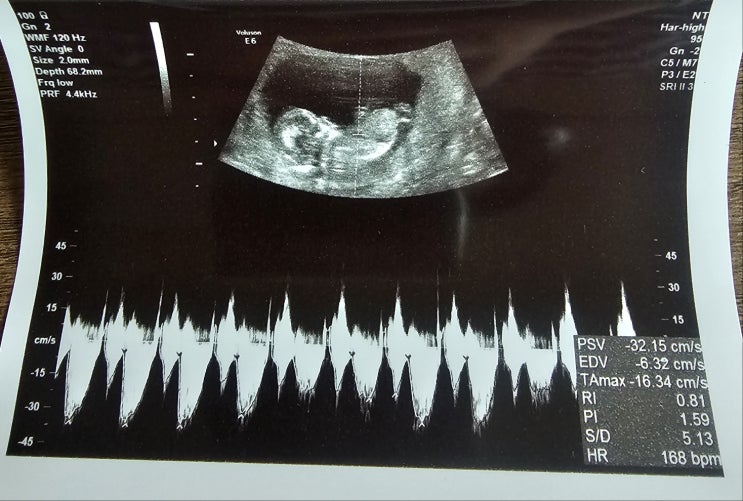

임신 12주 태아 크기 1차 기형아 검사 입덧 이야기

한 달 전만 해도 젤리 곰 같았던 우리 신이는 무럭무럭 자라 드디어 손가락 발가락 그리고 척추뼈까지 다 ...